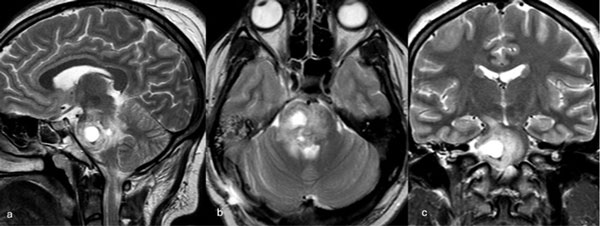

Caso 4: cavernoma bulbar

Una mujer de 53 años, con antecedentes de dos sangrados previos, consultó por un cuadro de perfil agudo caracterizado por tetraparesia asociada a compromiso de pares craneales bajos, que requirió instalación de una traqueostomía. La RM de encéfalo evidenció una malformación cavernomatosa en relación al bulbo izquierdo (Figura 9). Un mes después del último sangrado, la paciente fue sometida a una exéresis de la lesión mediante un abordaje suboccipital de línea media, vía intertonsilar (Figura 10), logrando una exéresis completa (Figura 11). Luego de la cirugía la paciente evolucionó con mejoría parcial de sus síntomas de ingreso, sin agregar nuevos déficits neurológicos.

Figura 9. RM preoperatoria de encéfalo. Se evidencia una lesión única intraaxial bulbotrigonal izquierda, que contacta la mitad inferior del piso del cuarto ventrículo, hiperintensa en T1 y T2, con vacíos de flujo que impresionan provenir de una malformación del desarrollo venoso, lo que sugiere una malformación cavernomatosa. A) Imagen en corte sagital ponderada en T1 posterior a la administración de gadolinio. B y C) Imágenes en corte axial ponderadas en T1 y T2, respectivamente.

Figura 10. Imágenes intraoperatorias bajo microscopía. Craneotomía suboccipital de línea media, con abordaje intertonsilar. A) Abordaje intertonsilar con disección telovelar hacia la derecha, abriendo el techo del cuarto ventrículo. B) Protrusión e identificación de la cápsula del cavernoma en relación al piso del cuarto ventrículo. C) Resección en bloque de la malformación cavernomatosa. D) Revisión del lecho, sin remanente.

Figura 11. RM postquirúrgica de encéfalo. Se evidencia una exéresis completa, sin daño del parénquima adyacente. A) Imagen en corte sagital ponderada en T1 posterior a la administración de gadolinio. B y C) Imágenes en corte axial ponderadas en T1 posterior a la administración de gadolinio y T2, respectivamente.